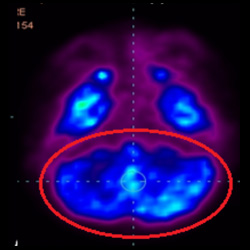

細胞治療前 PET CT 掃描顯示神經組織中的藍/黑色區域,表明腦癱引起的大腦損傷。

細胞治療后,藍色和黑色區域減少,并且看到更活躍的區域。這表明損傷減少并改善了大腦功能。

這證明細胞療法是治療腦癱兒童安全有效的方法。細胞療法可以更新大腦損傷的核心,并且可以通過 PET CT 掃描來監測大腦的改善情況。這些細胞療法與標準治療一起促進腦癱兒童的生長和改善。